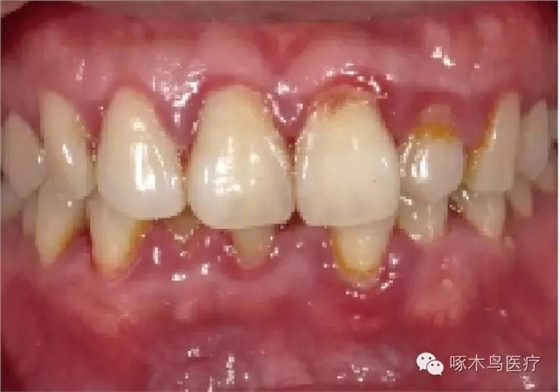

這些都是牙周病的早期癥狀?。。?p style="text-indent: 2em; text-align: left;">壹 牙周病有多可怕? 牙周病 常見的口腔疾病之一,是引起成年人牙齒喪失的主要原因。我國(guó)第三次口腔流行病學(xué)調(diào)查顯示,35歲以上人群牙周炎患病率高達(dá)80%-90%。更可怕的是,牙周病與心腦血管疾病、肺病、糖尿病都有著密切的關(guān)系。 肺病大量細(xì)菌借助食物返流被吸入氣管進(jìn)入肺部,導(dǎo)致支氣管炎、咽喉炎、扁 桃體炎和肺炎等。 五官口腔細(xì)菌可通過血管或者淋巴管,危害附近的耳、鼻、眼等器官。 心臟病約70%的心肌炎急性發(fā)作的誘因來源于牙周感染。 早產(chǎn)孕婦患牙齦炎,可能引發(fā)細(xì)菌進(jìn)入血液,感染胎兒,發(fā)生流產(chǎn)、早產(chǎn)或 新生兒體重過輕,還可能影響嬰兒大腦發(fā)育。 其中,最為明顯的是糖尿病。幾乎在所有針對(duì)牙周病的研究中都發(fā)現(xiàn),糖尿病患者的牙周疾病更為嚴(yán)重。 貳 如何治療牙周病? 牙周病高發(fā)人群 孕婦 煙民 精神高壓者 牙周病是一種慢性進(jìn)展的疾病,牙周組織一旦遭到破壞是不可逆的,一次,早期治療和日常預(yù)防就顯得尤為重要。 牙周病是由細(xì)菌感染引起的炎癥性疾病,最重要是去除牙齒、口腔黏膜和修復(fù)體表面的菌斑以及菌斑沉積物礦化形成的牙結(jié)石。已經(jīng)形成的牙結(jié)石和位于牙齦下的菌斑、結(jié)石,必須進(jìn)行專業(yè)的牙周治療才能清除。 早期的牙齦出血等牙齦炎癥,可以通過齦上潔治(即平時(shí)所說的“潔牙”、“洗牙”)來治療。 定期檢查,半年或一年進(jìn)行一次齦上潔治,能夠有效抑制牙周病的復(fù)發(fā)。 叁 如何預(yù)防牙周??? 日常生活中也要預(yù)防牙周病,目前最有效的方法是每天堅(jiān)持用正確方式刷牙,控制和消除牙菌斑的形成,按摩牙齦,促進(jìn)牙齦血液循環(huán),增強(qiáng)牙齦組織的抗病能力。 電動(dòng)牙刷、沖牙器的使用,可以清潔牙齒表面、牙縫中的細(xì)菌,改善口腔環(huán)境,有效預(yù)防牙周疾病的發(fā)生。 有些人認(rèn)為,牙周病并不可怕,牙齒掉了可以鑲假牙,卻不知道牙周疾病引起的牙齒缺失后,牙槽骨會(huì)加快吸收,牙床的高度和豐滿度下降,沒有很好的固位力,從而影響假牙的效果和使用壽命。 來源于啄木鳥醫(yī)療